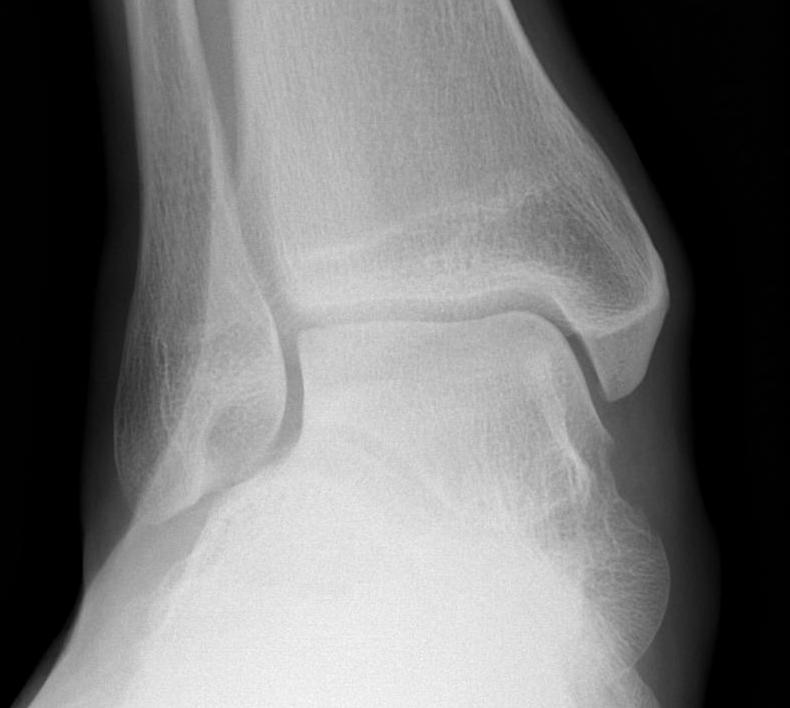

X-ray assessment

3 standard views

AP / Lateral / Mortise

Mortise

- AP with foot internally rotated

- should be symmetrical space around talus

Ankle Mortise ViewMortise

Increased tibio-fibular clear space  Overlap Increased medial clear space

Medial border of the fibula

Lateral border of the posterior tibia (incisura fibularis)

Measured 1 cm above the plafond

Overlap of the fibula and the anterior tibial tubercle

Medial talus to lateral medial malleolus

<5mm AP and mortise

> 6 mm AP view

> 1 mm mortise view

< 4mm

Equal to superior clear space